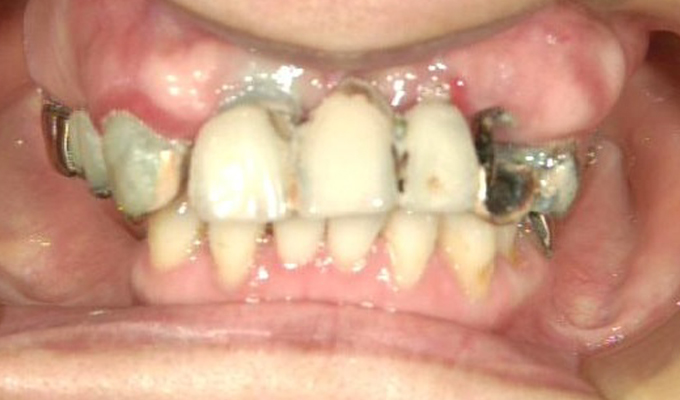

case5インプラント+メタルボンドブリッジ

初診時(2010年)

初回メンテナンス時(2012年)

最新メンテナンス時(2023年)

- 初診時の年齢

- 40代女性 (2010年)

- 主訴

- 5年ほど前に上に総入れ歯を作った。(マグネットタイプ)食事してたら人口歯が取れてしまった。インプラントに興味がある。40代なので入れ歯はやっぱり嫌、とのことでした。

- 治療内容

- 上・・・虫歯の根だけの歯が数本残っているためすべて抜歯し仮義歯作成しました。最終的には8本インプラントを埋入し上部構造はメタルボンドです。

下・・・保存できる下の歯はメタルボンドブリッジにし、奥歯のない部分に3本インプラントを埋入しました。治療期間は2年ほどかかりましたがしっかり食事ができるようになったので嬉しいと、満足していただけました。

以降定期的にメンテナンスに来院いただき11年経過してもいい状態を維持されています。